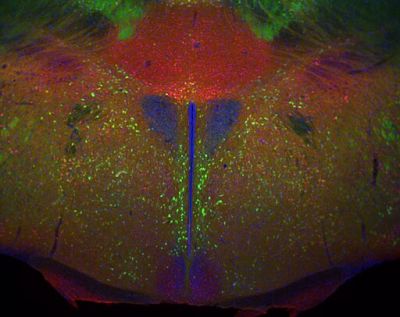

Calretinin and DAPI – histology slide

The hypothalamus from a D2-eGFP (green) transgenic mouse stained for calretinin (red) and DAPI to show nuclei.